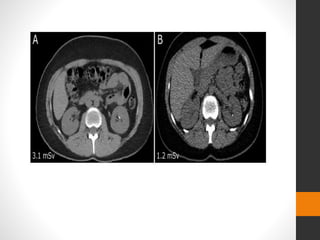

โ€ข CT KUB is very good at picking up small and large calcified

stones in the kidneys

โ€ข unenhanced CT scan of the abdomen and pelvis very narrow

cuts taken through the kidneys and bladder areas

โ€ข contrast obscures calcific densities

โ€ข the patientโ€™s bladder is filled, which facilitates viewing the

ureterovesical junction

Advantages of CT scanning

โ€ข It can reveal other pathology (e.g., AAAs, appendicitis,

pancreatitis, cholecystis, ovarian disorders, diverticular

disease, renal carcinoma).

โ€ข It can be performed quickly (< 5 min acquisition time)

โ€ข It avoids the use of IV contrast materials.

โ€ข The density of the stone can assist in predicting stone

composition and response to shockwave lithotripsy.

โ€ข Spiral CT is now increasingly replacing the IVU

โ€ข sensitivity of 94%, and specificity of 97%

โ€ข exposes the patient to a significant radiation

โ€ข Essentially all ureteric calculi are radiopaque on CT

โ€ข Calculi usually demonstrate a rim of soft tissue, which helps

distinguish them.

โ€ข The obstructed kidney may also be enlarged

โ€ข There is often stranding within the perinephric fat

โ€ข The pyramids may normally appear remarkably dense on

unenhanced CT (white pyramid sign)